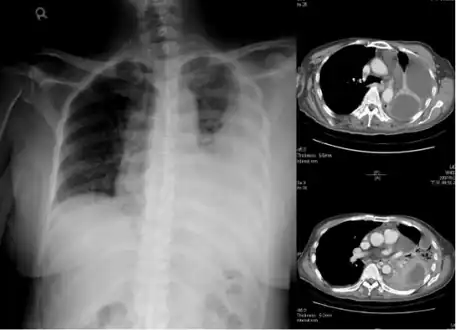

Lungs

Empyema